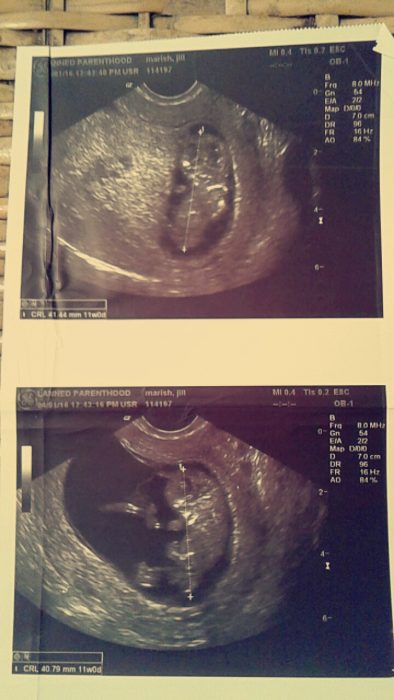

The Planned Parenthood staff could tell I was very undecided and not sure I wanted to go through with it. I asked for the ultrasound, which kills me to this day. It cost $100 to get the ultrasound in my hand. I remember being angry and making them charge it to the father. I remember looking at it, saying, “That’s a baby… our baby.” I took the ultrasound, knowing when we came that following week there was no way I’d be able to go through with it. But I did.